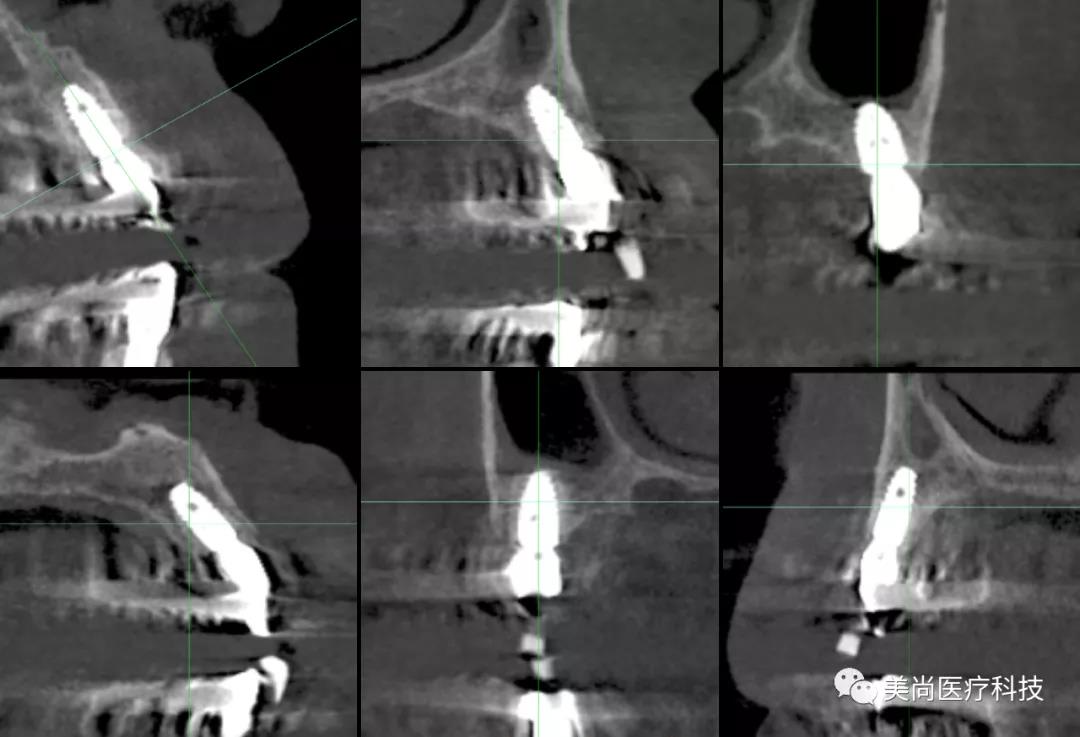

术前X-ray